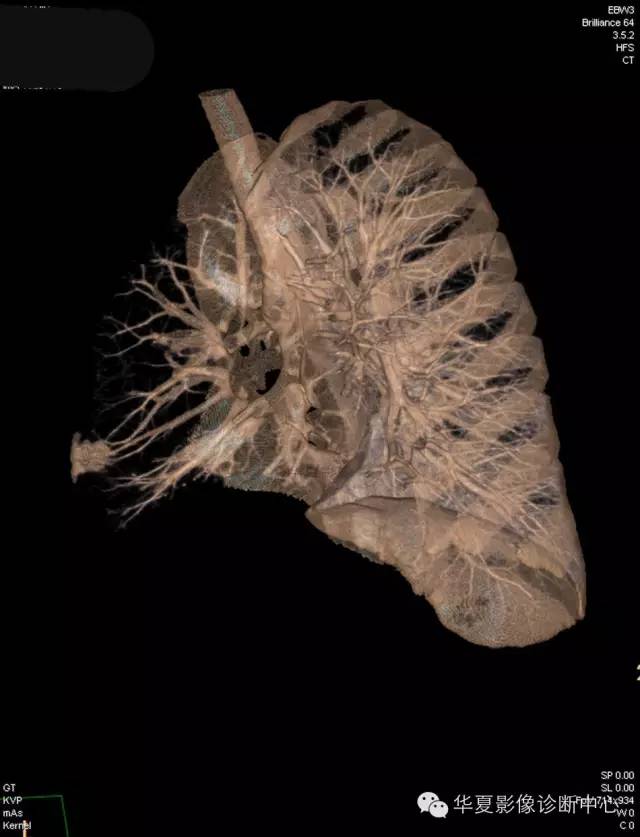

【病例学习】典型周围型肺癌CT病例一例

女,56岁,其父因肺癌去世,自觉胸部疼痛不适来诊要求拍胸片。

1.右肺上叶:肺组织1块,大小13×4×7cm。切面棕红色。2.右肺上叶肿物:灰白色组织一块,大小3×1×1.5cm。切面灰白色。3.右肺中叶结节:灰白色绿豆大组织1块。4.淋巴结:灰黑色绿豆大组织1块。

(右)肺中分化鳞状细胞癌。浸及胸膜。支气管残端切净。淋巴结未见癌转移(0/10)。